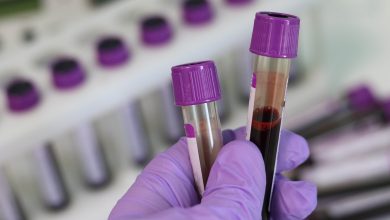

Programa para aprimorar a triagem do HIV aumenta os testes em clínicas de atendimento urgente e departamentos de emergência

Crédito: Pixabay/CC0 Public Domain Um novo estudo de pesquisadores da Intermountain Health em Salt Lake City constata que um programa…